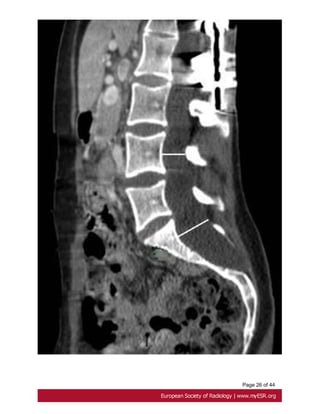

Fig. 22: Reformated CT scan shows spondilolisthesis and scalloping at levels S1 and S2.

• Spondylolisthesis

Analysis of the Marfan lumbar spine found a higher prevalence of spondylolisthesis,

corresponding to the displacement of a vertebra in relation to the vertebrae [5]below[30].

Fig. 22 on page 35

Page 36 of44 Fig. 22: Reformated CT scan shows spondilolisthesis and scalloping at levels S1 and S2.